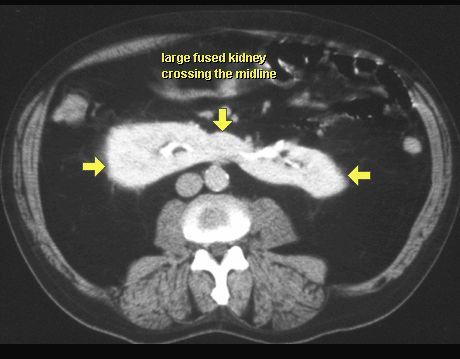

NERKA PODKOWIASTA

TK